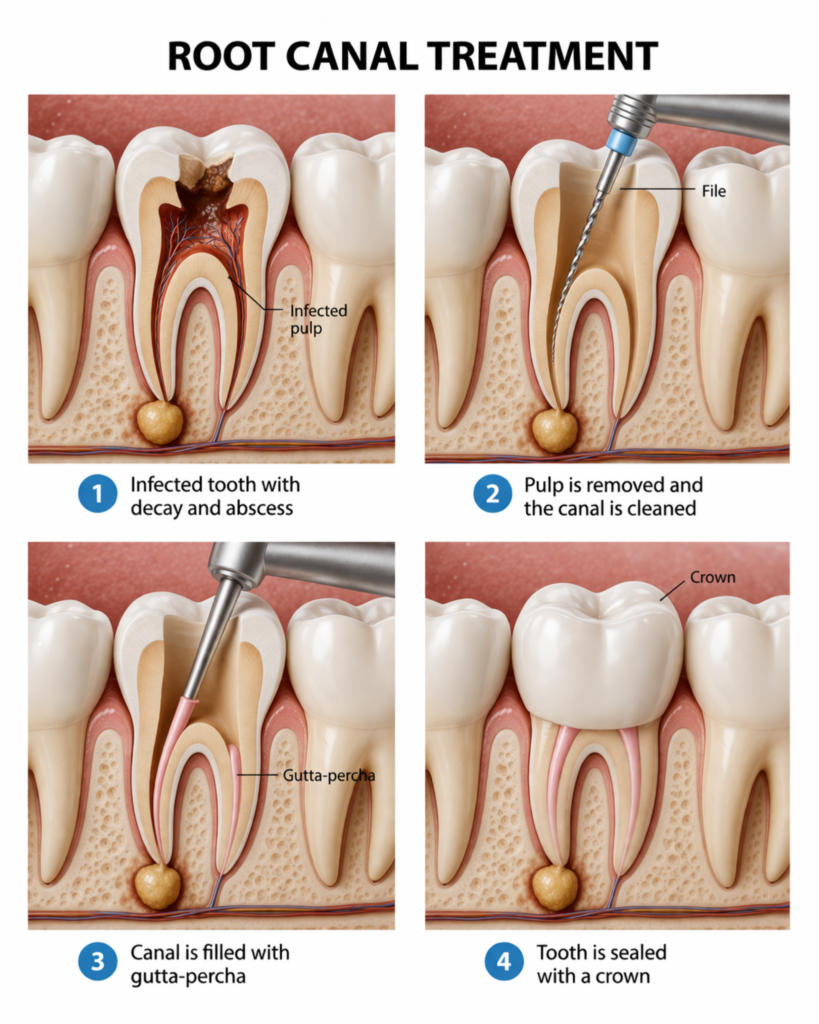

Signs You Need a Root Canal Treatment

It usually starts with something small. A slight discomfort while eating. A sharp feeling when something cold or hot touches your tooth. You ignore it. Because it’s not constant. It comes and goes. So it doesn’t feel serious. But then…it stays longer than it should. That same tooth starts reacting more often. The pain gets [...]

A Simple Guide to Root Canal Treatment and Dental Care

The words “root canal treatment” always seem to bring fear into people’s minds, especially because they associate it with pain.

Restore Your Tooth, Relieve Your Pain with Tooth Root Canal in Karachi at Altamash Dental Clinic

Tooth pain can be tough to ignore because it loudly impacts your mood, your eating habits, and even your daily routine